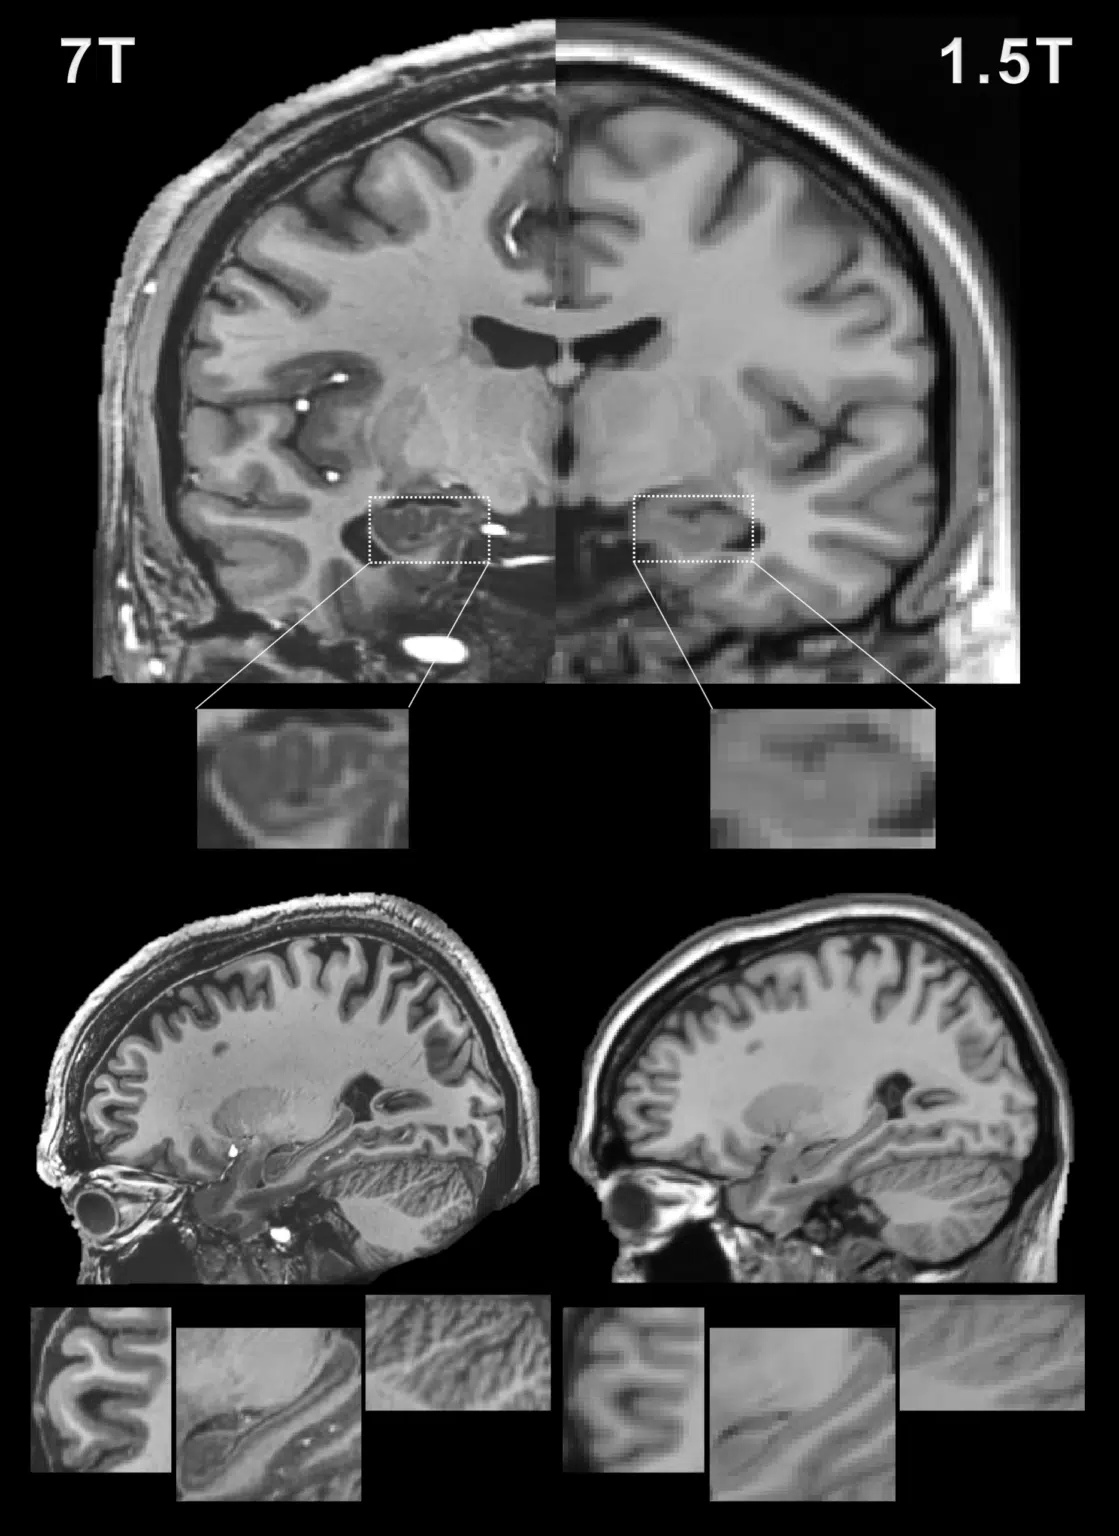

MR Physics

Magnetic resonance imaging (MRI) offers a unique opportunity to non-invasively study the human brain, equipped with a wealth of contrasts (to disentangle structures and functions), and a favourable window of spatiotemporal resolution. But to expand its clinical and neuroscientific scope, MRI has to become faster and more robust. A key ingredient to this end is a mechanistic understanding of the imaging physics, and its consideration in the way we acquire and reconstruct MR images. This comprises the choice of optimal sequence and sampling strategy for the target application (e.g., spiral trajectories for short echo-time) a detailed characterization of both hardware imperfections (e.g., heating/field drift and trajectory errors) and subject-related noise sources (e.g., breathing, motion) giving rise to image artifacts, the accurate inclusion of this information into an expanded signal model of the MR imaging process and advanced image reconstruction techniques capable of inverting these intricate models. This integrated approach leads to better imaging data tailored to the analysis and diagnostic purpose of the MR exams. The characterization of each scan’s imaging peculiarities allows for better comparability of multi-site studies in the era of big data. At the other end of the spectrum, personalized medicine requires individualized MR imaging protocols that are enabled by flexible and extendable signal models and reconstructions.